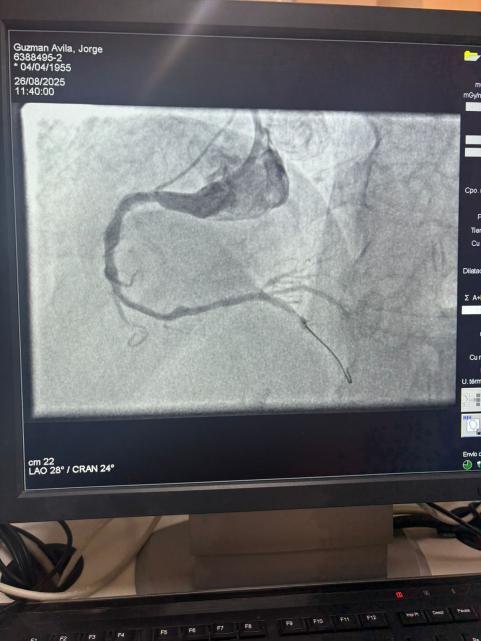

Siamo orgogliosi di condividere un caso straordinario dell'ospedale Sótero del Río, Cile, dove il Dr. Martín Valdebenito ha trattato con successo una lesione fortemente calcificata nell'arteria coronaria destra (prima curva) utilizzando il nostro sistema di catetere di dilatazione del palloncino Vesscrack Coronary IVL.

La procedura ha ottenuto risultati eccezionali, con la regione calcificata effettivamente incrinata e il flusso della nave ripristinato. Questo segna un'altra pietra miliare nell'espansione dell'accesso globale a soluzioni avanzate per la calcificazione coronarica complessa.

Il confronto tra le immagini angiografiche pre-procedura e post-procedura dimostra chiaramente il significativo impatto clinico della nostra tecnologia IVL.